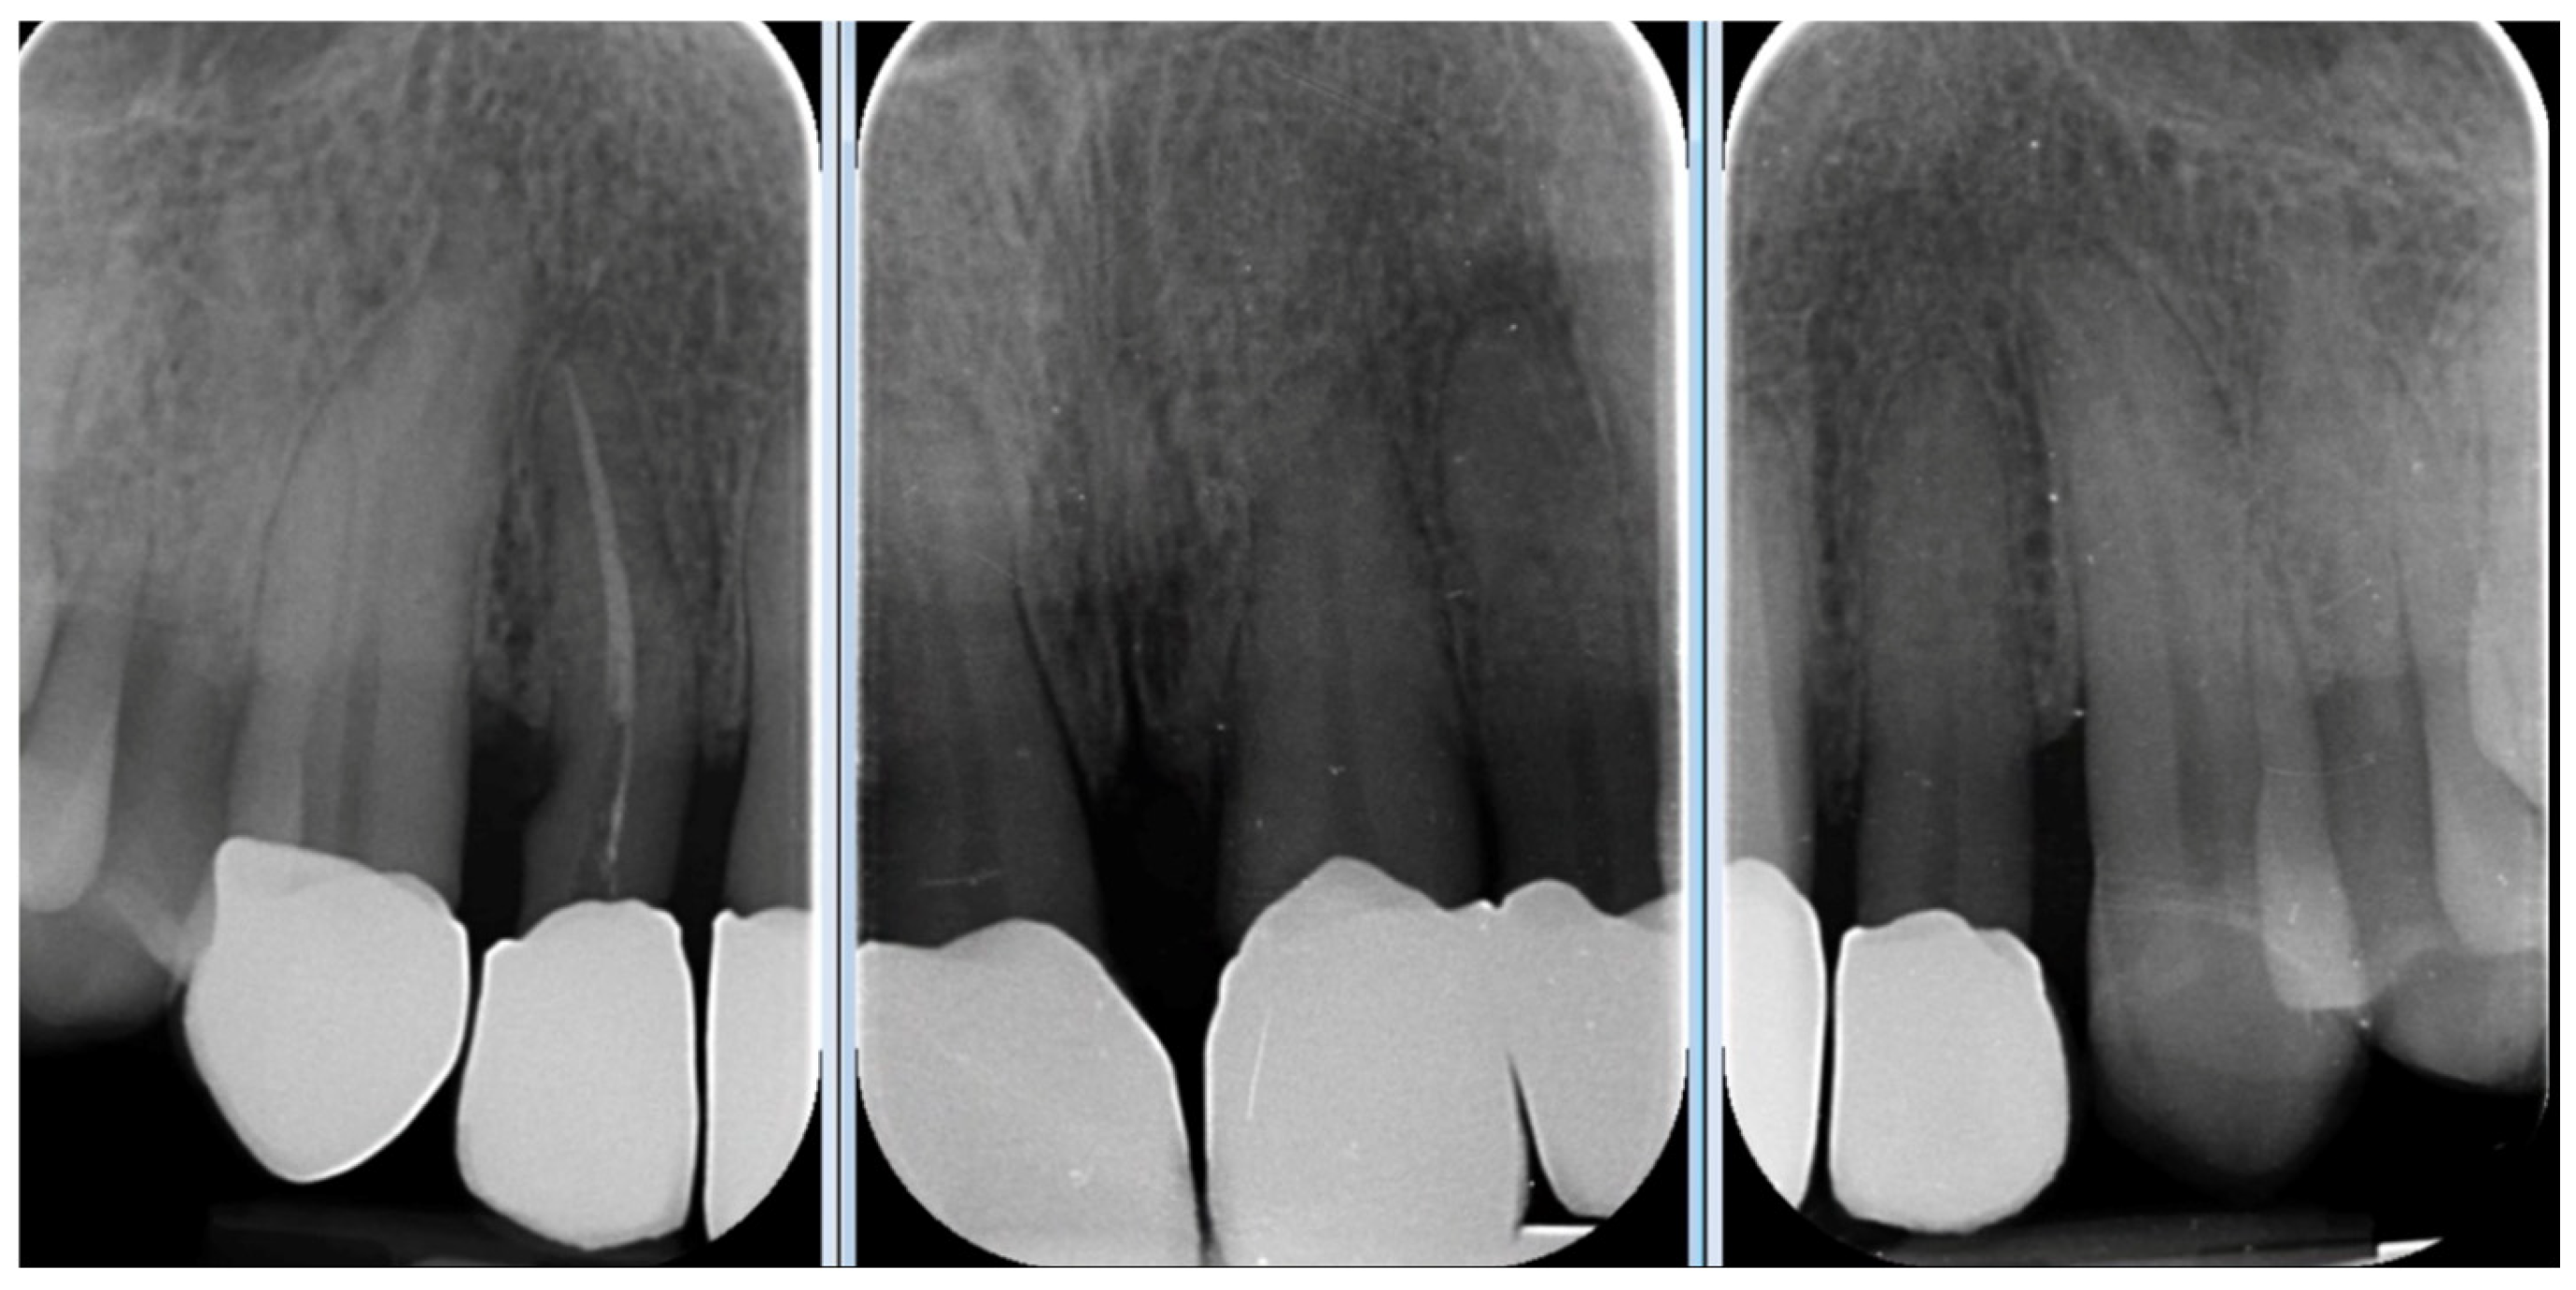

A 39-year-old male patient presented for prosthetic rehabilitation of the anterior maxillary region, primarily motivated by aesthetic concerns and periodontal health improvement. The patient reported a history of smoking (10–15 cigarettes per day since he was 18 years old) and had been diagnosed with localised stage III, grade B periodontitis. Even if the defect is mostly horizontal and localised to the II sextant, stage III was defined due to the bone loss extending to the middle third of the roots and the probing depth is ≥6 mm in this sextant. Moreover, smoking represents a risk factor able to classify the case as grade B. Initial clinical and radiographic evaluation (Figure 1) revealed the absence of all four third molars, the presence of conservative restorations on teeth 1.6, 3.7, and 4.6, and evidence of horizontal alveolar bone resorption in the regions corresponding to teeth 1.4 and 2.3. A conoid morphology was noted in the upper left lateral incisor.

Figure 1. Initial radiographic assessment.

Figure 20. Four-year follow-up radiographic examination.

At the four-year follow-up, clinical evaluation demonstrated stable soft and hard tissues, with no biological or mechanical complications observed throughout the entire follow-up period.